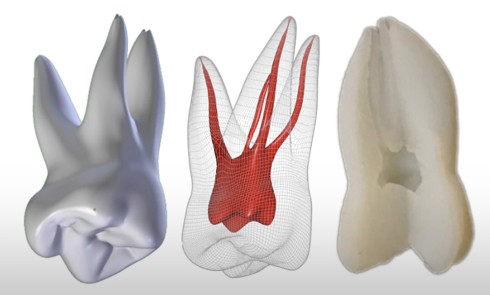

La première consiste en la persistance d’une infection intraradiculaire au sein de la zone apicale d’un canal riche en ramifications et en canaux accessoires ou d’un canal oublié (fig. 4) :

ces infections sont caractérisées par une flore microbienne particulièrement résistante correspondant aux micro- organismes résiduels à la suite d’une infection primaire ou secondaire. Ces micro-organismes sont généralement présents sous forme d’un biofilm au sein duquel ces derniers, noyés dans une matrice polysaccharidique adhérente aux parois canalaires [3], sont significativement plus résistants que ceux simplement en suspension [48]. Ils peuvent dès lors résister aux diverses solutions d’irrigation et médicaments intracanalaires, mais également survivre dans un environnement nutritionnel restreint [2, 5, 47]. Lors de la mise en forme canalaire, certaines régions, du fait de la complexité anatomique des racines, ne peuvent être ni débridées mécaniquement ni obturées. Ainsi, des colonies bactériennes sous forme de biofilm sont fréquemment retrouvées dans les ramifications apicales, dans les isthmes et au sein de concavités inaccessibles de la paroi radiculaire [19]. Ces zones représentent des niches de colonisation bactérienne pouvant par la suite contrarier la guérison apicale. Les micro-organismes retrouvés sont principalement Enterococcus faecalis et Candida albicans [41], même si d’autres espèces, plus généralement retrouvées dans les infections primaires comme Propionibacterium, ont été également mises en évidence [30, 32].